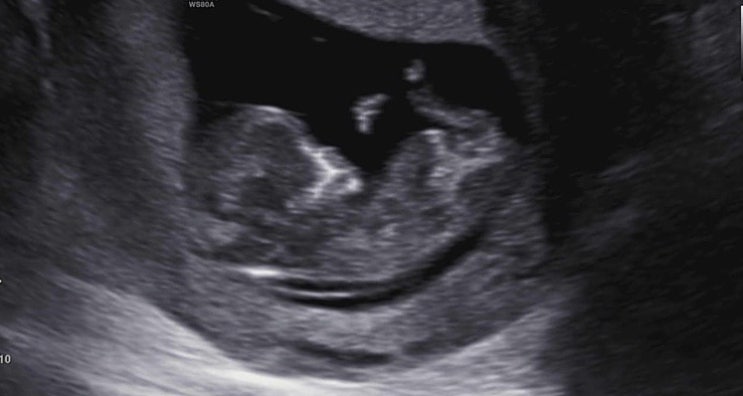

임신 12주) 1차 기형아 선별 검사, 각도법 성별 유추

사실은 11주 6일에 진행한 1차 기형아 선별 검사인데 어차피 하루 차이니까 편의상 12주라고 하겠다! 12주...